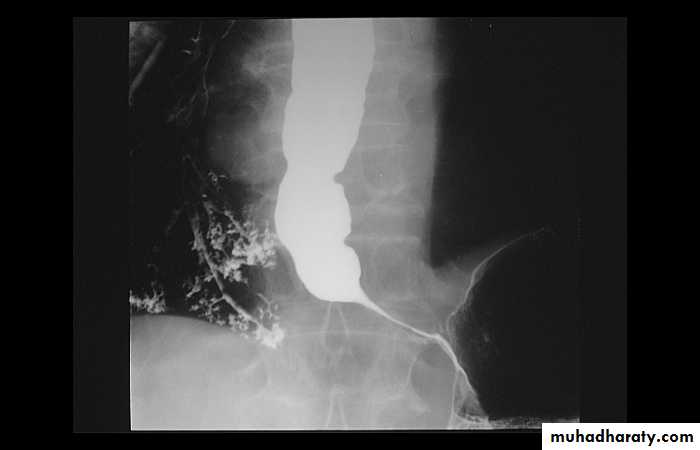

Narrowing :

1-the narrowing is Constant Short length (confined to cardia).

2-Regular and smooth.

3- No shouldering sign.

4-Tapering (Tip of pencil , cigar shape) Under left dome of diaphragm.

Achalasia continue

5. DILATATION (Sac like in proximal part )6-Undulating or spiky out line due to sluggish peristalsis.

7 Non- homogeneity of Barium due to food particles.

8-Air Barium level.

10-Absence of fundal gas shadow.